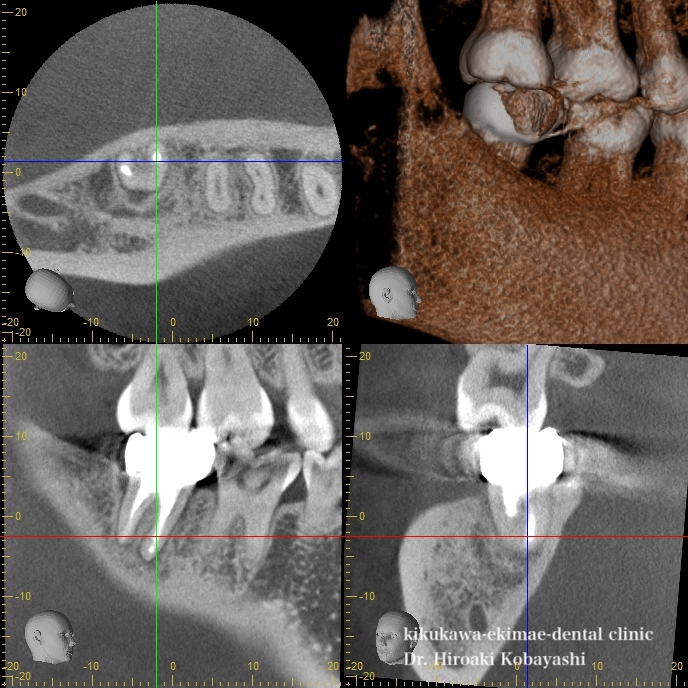

上の写真と比べると骨が再生し、根のがしっかりと固定されたのがお分かりかと思います。例え、歯の神経が無くなったとしてもセルフケアや力のセルフコントロールがなされば長期に渡って歯を残すことができます。それは抜いてインプラントをするよりも予知性のある治療になります。

また、他の方ですが、歯の上からのアプローチでは改善されない症例に関しましては歯根端切除や再移植によって歯を残すことも可能です。